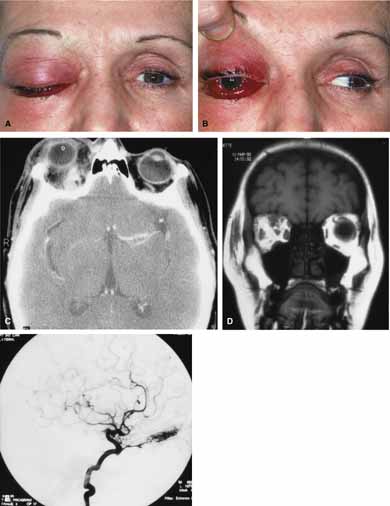

| Cartoid cavernous sinus fistula (CCSF) is the most common arteriovenous